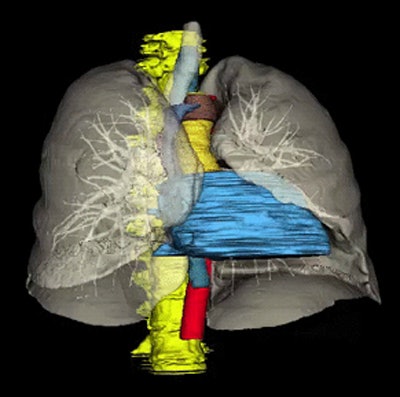

Multiorgan segmentation

The fully automated software identifies eight organs using multiatlas label fusion and the relative position of the node to these organs to assign the IASLC station location.

First is spine segmentation performed using a watershed algorithm that identifies the spine in yellow (the organs are all color-coded). Next comes tracheal and lung segmentations, which use thresholding and morphological operations. Finally, come the other organs, including the esophagus and aortic arch, pulmonary trunk, ascending and descending aortas, superior vena cava, azygous arch, and the heart using the multiatlas technique with joint label fusion, Summers said.

These atlases are then registered to the target image segment and merged via joint label fusion to generate the final segmentation, Summers said.